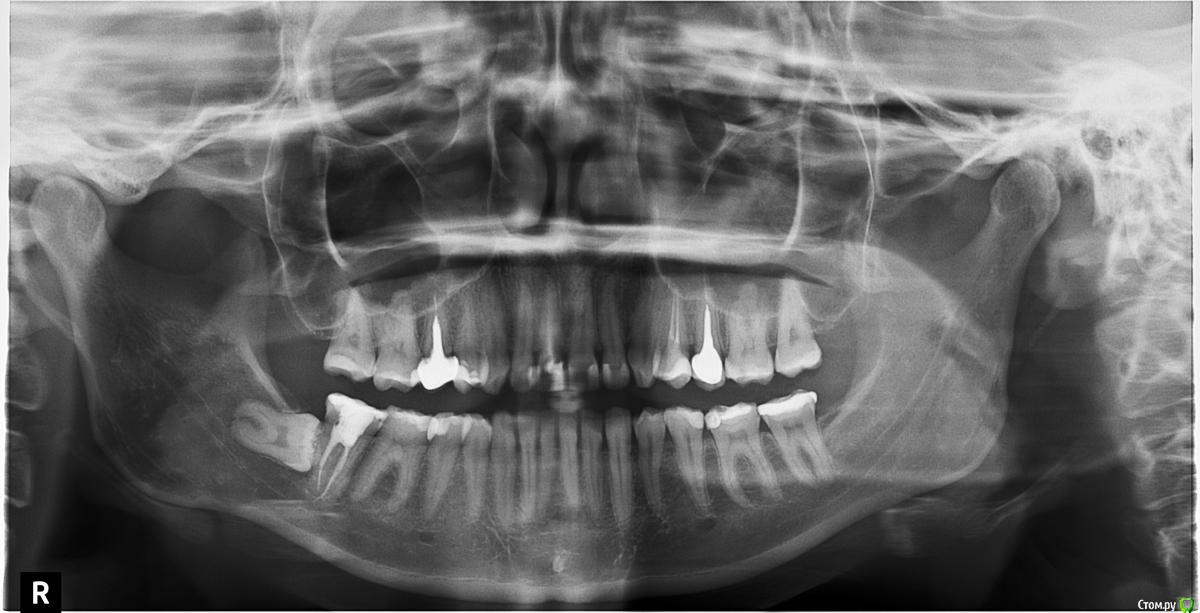

A.T.Bulatova Опубликовано 3 декабря, 2015 Поделиться Опубликовано 3 декабря, 2015 Здравствуйте! Подскажите пожалуйста! Возникла следующая проблема: на 47 зубе было решено менять пломбу, потому что возник кариес. Пломбу поменяли, зуб потом разболелся, депульпировали. После удаления нерва (25.11.15) Зуб болит при надкусывании, на горячее/холодное не реагирует. Были поставлены гуттаперчивые штифты. Закрыт постоянной пломбой (27.11). С 28.11 Началось онемение подбородка - больше по центру, и чуть в сторону леченной 7-ки, и немного нижней губы. Может ли парастезия быть связана с лечением 7ки? Снимок сделан сразу после установки постоянной пломбы на 7-ку. 8-ка до лечения 7-ки вообще не была замечена, и никаких неудобств ранее не предоставляла. Лечащий врач говорит ждать, пока не пройдет боль при кусании, потом уже решать - открывать заново 7-ку или нет, чтобы прошло онемение. Из-за боли переживаний нет - я понимаю, что такое бывает, а вот онемение сильно смущает.Как быть теперь? Ссылка на комментарий

Ker Опубликовано 3 декабря, 2015 Поделиться Опубликовано 3 декабря, 2015 (изменено) Может ли парастезия быть связана с лечением 7ки? Снимок сделан сразу после установки постоянной пломбы на 7-ку. Может. Видимо немного материала вышло за верхушку.Есть прицельный снимок? Изменено 3 декабря, 2015 пользователем Ker Ссылка на комментарий

A.T.Bulatova Опубликовано 3 декабря, 2015 Автор Поделиться Опубликовано 3 декабря, 2015 Прицельный снимок у врача, к сожалению, выложить его не могу. Его делали после пломбировки каналов - все было в норме. После онемения эти снимки еще раз посмотрели 2 терапевта и сказали, что выхода материала нет, и скорее всего парастезия связана с анестезией - либо травмой иголкой (?), либо просто побочное действие.Сможет ли КТ прояснить ситуацию? Если это все таки выход материала, то придется зуб удалять или распломбировывать?Спасибо большое за ответы!(КТ собираюсь делать сегодня) 1 Ссылка на комментарий

A.T.Bulatova Опубликовано 3 декабря, 2015 Автор Поделиться Опубликовано 3 декабря, 2015 К тому же, меня немного смущает тот факт, что пломбировали каналы 25.11, а онемение пришло ко мне только 28-29.11. Такое возможно при травме нерва? Я обязательно выложу КТ и прицельный снимок.Просто сейчас очень страшно Ссылка на комментарий